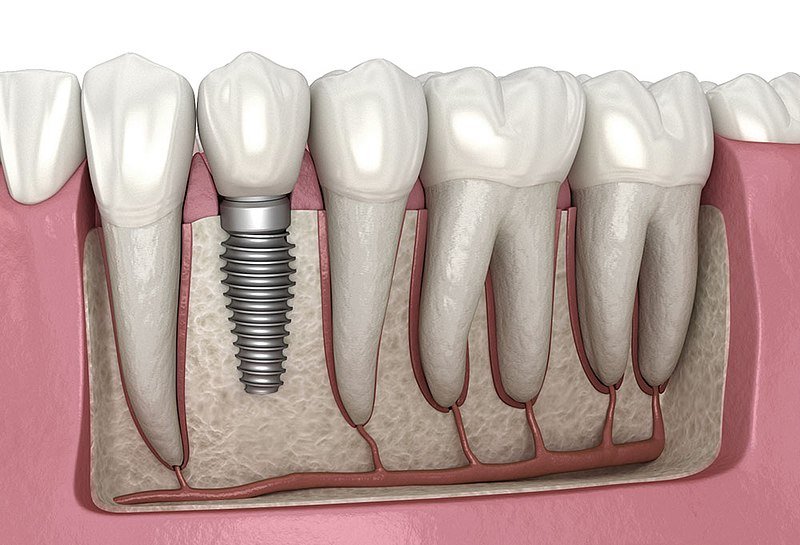

He has great experience in the field of Periodontology and Dental Implats. And well-known consultant implantologist in many clinics across Gujarat.

We visited sure cure dental clinic for my mother in laws treatment. We overall had very pleasant and comfortable experience. Dr akshay did a great job with root canal treatment and cap over that and also with implant, which was so comfortable and painless. We were anxious about treatment before going there. But we had it going so smooth.

I got my root canal treated by Dr akshay vala. It was really pain less. And my parents got their implats done at sure cure dental clinic by Dr akahay. And now they are also very satisfied. Thank you sir.